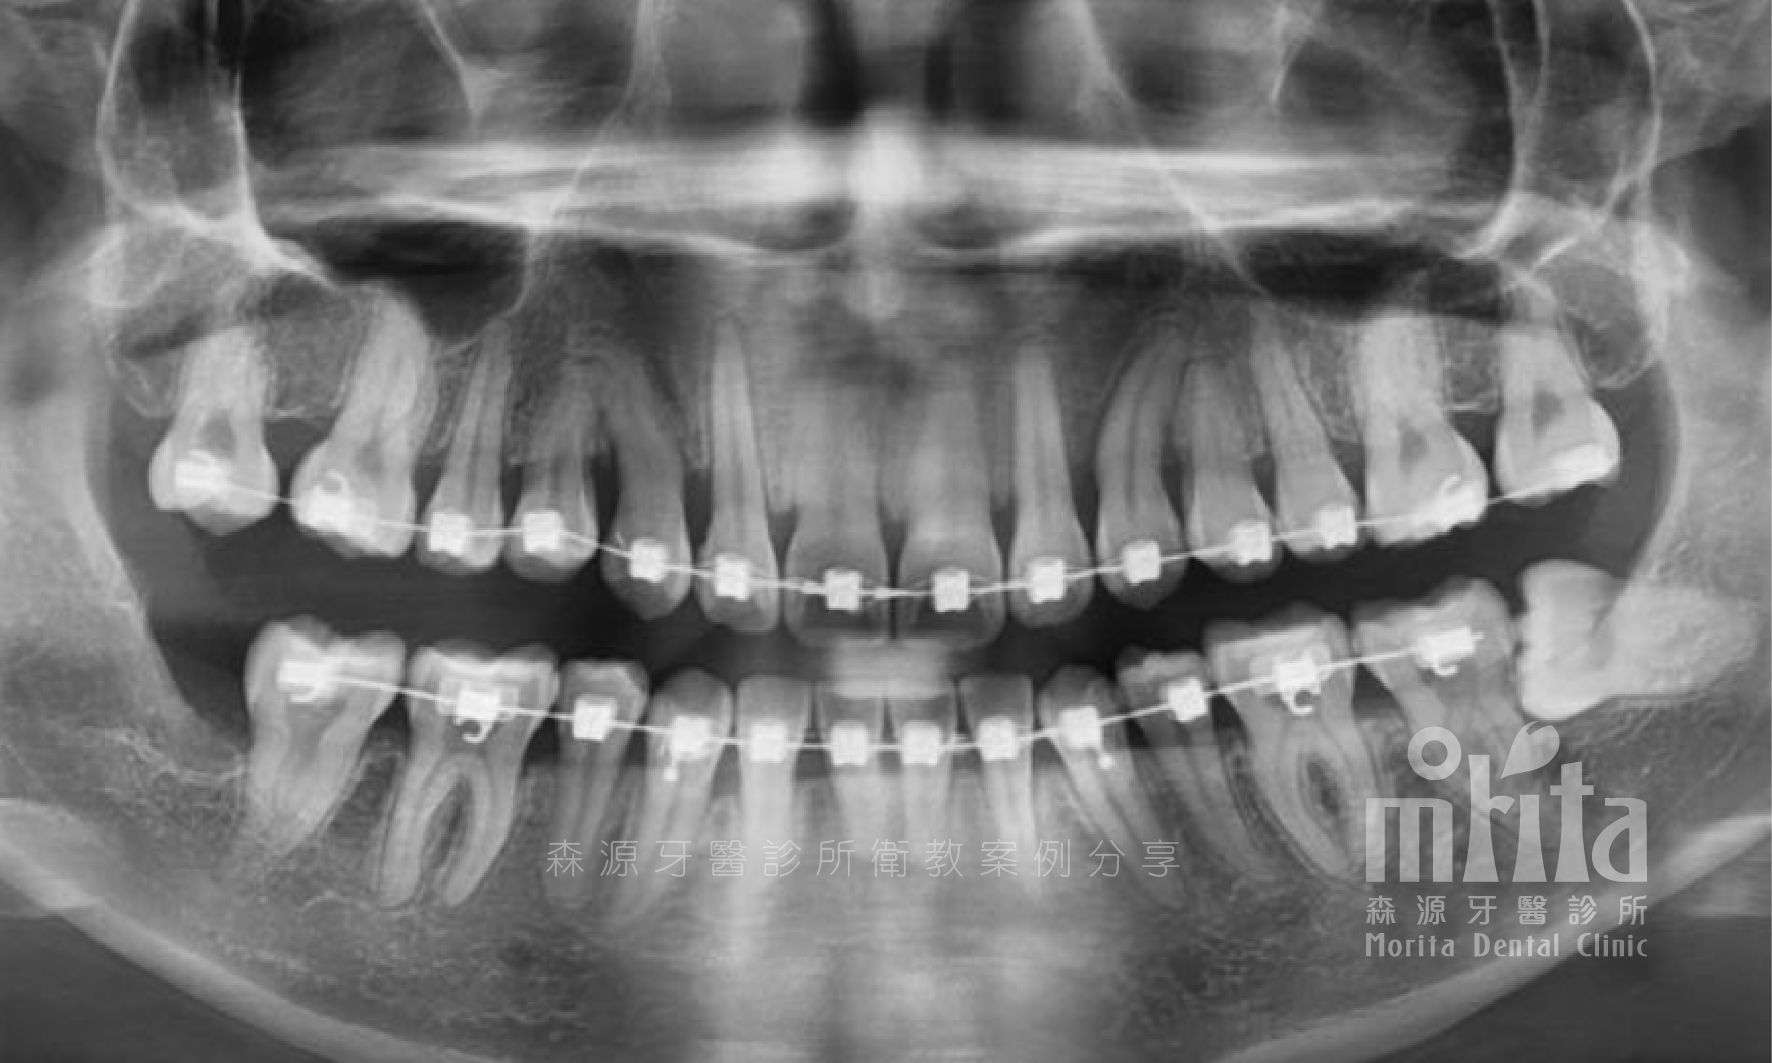

阻生齒 Impaction

犬齒是上顎恆齒中較晚萌發的牙齒,常常會因為被鄰近牙齒佔據的生⻑空間而無法順利萌發,困難的阻生齒常常會需要藉助手術露出,以及搭配特殊裝置,才有機會順利拉出。